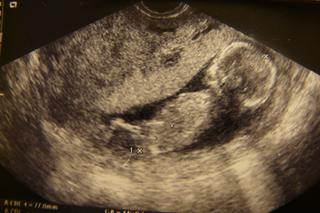

@nelynka18 Krásna fotečka 🙂

@nellynka super fotka, gratulujem k páriku, normálne si ma presvedčila aby som išla na 3Dčko už teraz 🙂 Už sa neviem dočkať 🙂 Zajtra sa objednám 🙂 Naozaj to tam pekne vidieť, máte to isté 🙂

@zuzanka.j pekna fotka,male je tam take vysponovane.bude to gymnasta 😉 pekne.....

kocky, ten pipik je dole pri jednej nozicke pod ruckou akoby rovno pod zapastim. Taky maly vyrastok 🙂))) Mam aj videjka a tak je to castejsie vidno, len tu sa to neda dat. Inak ja som skor chcela dievcatko, aby sa spolu hrali s Kristinkou, ale v podstate je to jedno, hlavne nech je babatko zdrave.

@nellynka 🙂 ďakujeme za vysvetlenie, ja som si to aj stiahla do PC, celú fotku, zväčšovala, no neviem sa vyznať.. nožička je dole? ci hore? lebo to hore mi pripada ako krk, potom tam vidim tu jednu rucku.. a potom dole nieco, ako cast nozicky.. nevies to zakresliť skicárom? aby sme mali jasno, kde hľadať? No už sa vidím, ako študujem moje fotky, aké je to pohlavie.. ja chcem ísť na 3D v 20 TT. 🙂

@nellynka ano teraz ho uz vidim 😉